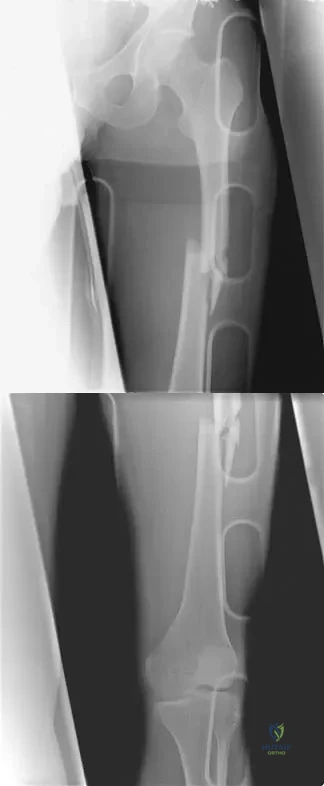

A 68-year-old man fell off a 20-foot mountain cliff and was seen in the emergency department the following morning. A radiograph is shown in Figure 12. He is a nonsmoker with medical comorbidities of hypertension and hypercholesterolemia that is well controlled with medicine and diet. Capillary refill and sensation are intact distally and the patient is able to move his toes with mild discomfort. Serosanguinous fracture blisters are present laterally, and the foot is swollen and red. What is the most appropriate management?